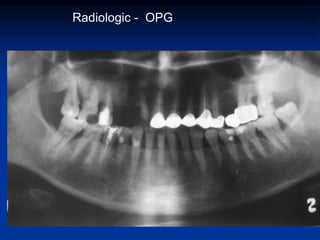

 Examenului R-logic (metoda cea mai informativă - OPG)

Radiologic - OPG